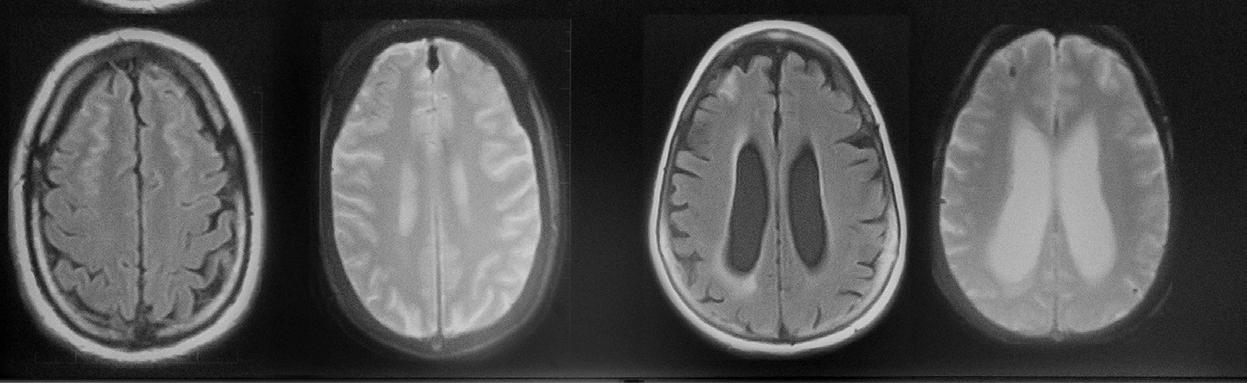

Eating Ultra-Processed Foods Impacts Muscle Quality

Adiet high in ultra-processed foods is associated with higher amounts of fat stored inside thigh muscles, regardless of the amount of calories consumed or level of physical activity, according to a study presented by a team of UCSF researchers at the 2024 RSNA meeting. Higher amounts of intramuscular fat in the thigh could also increase the risk for knee osteoarthritis.

“The novelty of this study is that it investigates the impact of diet quality, specifically the role of ultra-processed foods in relation to intramuscular fat in the thigh muscles assessed by MRI,” said author Zehra Akkaya, MD, researcher and former Fulbright Scholar in the Department of Radiology and Biomedical Imaging at the University of California, San Francisco. “This is the first imaging study looking into the relationship between MRI-based skeletal muscle quality and quality of diet.”

For the study, researchers analyzed data from 666 individuals who participated in the Osteoarthritis

Initiative who were not yet affected by osteoarthritis, based on imaging. The Osteoarthritis Initiative is a nationwide research study, sponsored by the National Institutes of Health, that helps researchers better understand how to prevent and treat knee osteoarthritis.

“Research from our group and others has previously shown that quantitative and functional decline in thigh muscles is potentially associated with onset and progression of knee osteoarthritis,” Dr. Akkaya said. “On MRI images, this decline can be seen as fatty degeneration of the muscle, where streaks of fat replace muscle fibers.”

Of the 666 individuals, (455 men, 211 women) the average age was 60 years. On average, participants were overweight with a body mass index (BMI) of 27. Approximately 40% of the foods that they ate in the past year were ultra-processed.

Figure 1. Axial T1-weighted bilateral thigh MR images and magnified frames providing a closer look at the areas in lateral aspects of quadriceps femoris muscles (knee extensors) from two obese, female participants, aged 58 (A) and 62 years (B), respectively. In A, the thigh muscles on both sides demonstrate abundant fatty streaks, consistent with a high Goutallier grade of 45 for this participant, whose diet from the past 12 months consisted 68% of ultra-processed foods. In B, the thigh muscles show fewer fatty streaks as highlighted in the magnified image, consistent with a low Goutallier grade of 17 for this participant, whose diet contained only 36% ultra-processed foods.

The researchers found that the more ultra-processed foods people consumed, the more intramuscular fat they had in their thigh muscles, regardless of energy (caloric) intake.

“In an adult population at risk for but without knee or hip osteoarthritis, consuming ultra-processed foods is linked to increased fat within the thigh muscles,” Dr. Akkaya said. “These findings held true regardless of dietary energy content, BMI, sociodemographic factors or physical activity levels.”

Targeting modifiable lifestyle factors— mainly prevention of obesity via a healthy, balanced diet and adequate exercise—has been the mainstay of initial management for knee osteoarthritis, Dr. Akkaya noted.

“Osteoarthritis is an increasingly prevalent and costly global health issue. It is the largest contributor to non-cancer related health care costs in the U.S. and around the world,” Dr. Akkaya said. “Since this condition is highly linked to obesity and unhealthy lifestyle choices, there are potential avenues for lifestyle modification and disease management.”

By exploring how ultra-processed food consumption impacts muscle composition, this study provides valuable insights into dietary influences on muscle health.

“Understanding this relationship could have important clinical implications, as it offers a new perspective on how diet quality affects musculoskeletal health,” Dr. Akkaya said.

Part A Part B

Mean Values (n=666) Results for the relationships between UPF consumption and thigh muscle Goutallier Grades Mean

Mean GG add (SD) (Range=0-24)

Part A presents the mean values for the predictor (UPF) and outcomes (Goutallier grades) for the study cohort. Part B presents the results from linear regression models for all thigh muscles (GG all), knee extensors (GG ext), knee flexors (GG flex) and thigh adductors (GG add). Beta coefficients represent the change in GG for 1 SD increase in UPF. Models were adusted for age, sex, race, body mass index, total daily calorie intake, education and income levels, physical activity scores and depression. Bold letters indicate statistically significant results. CI: Confidence interval; GG: Goutallier grade; SD: Standard deviation; UPF: Ultra-processed foods.